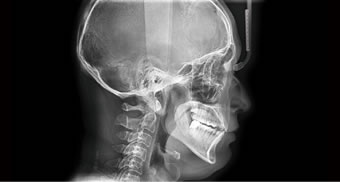

Cephalo:スキャンタイプ、ワンショットタイプを選択可能に

セファロ(頭部X線規格写真)はスキャンタイプと撮影時間の短いワンショットを選択して行います。モーションアーチファクトの少ない鮮明な画像診断を行うことができます。